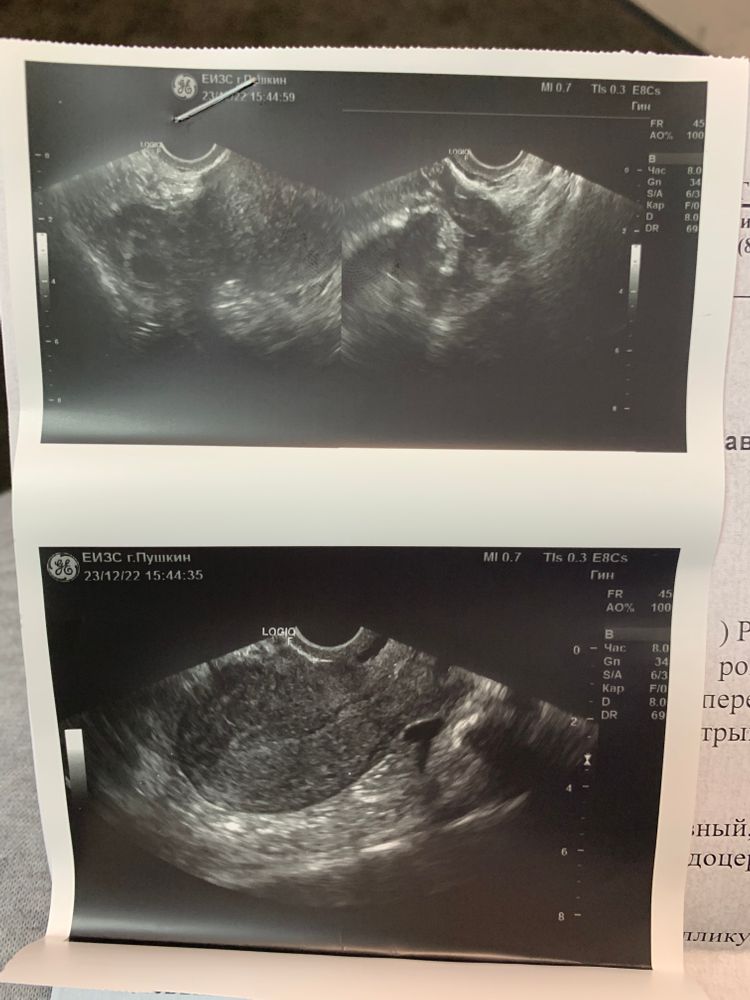

стала отслеживать О, уже 14 день цикла, тесты со слабой 2 полоской, что говорит об отсутствии повышения лг. Пошла на узи сейчас, врач нахамила, что я пришла зря и О отслеживать надо аж 6 раз в месяц по узи( 5-9, 12-14, 21-23. Я сказала, что если есть дф, то его видно. Она сказала ничего нет, но и не отменила тот факт, что О может быть и поздней. Вот думаю продолжать делать тесты или забить.

я сходила на узи вчера ( 17дц), дф 16,6))) сказали ждать через 2-3 дня, значит поздняя

только эндометрий мне не нравится 7мм